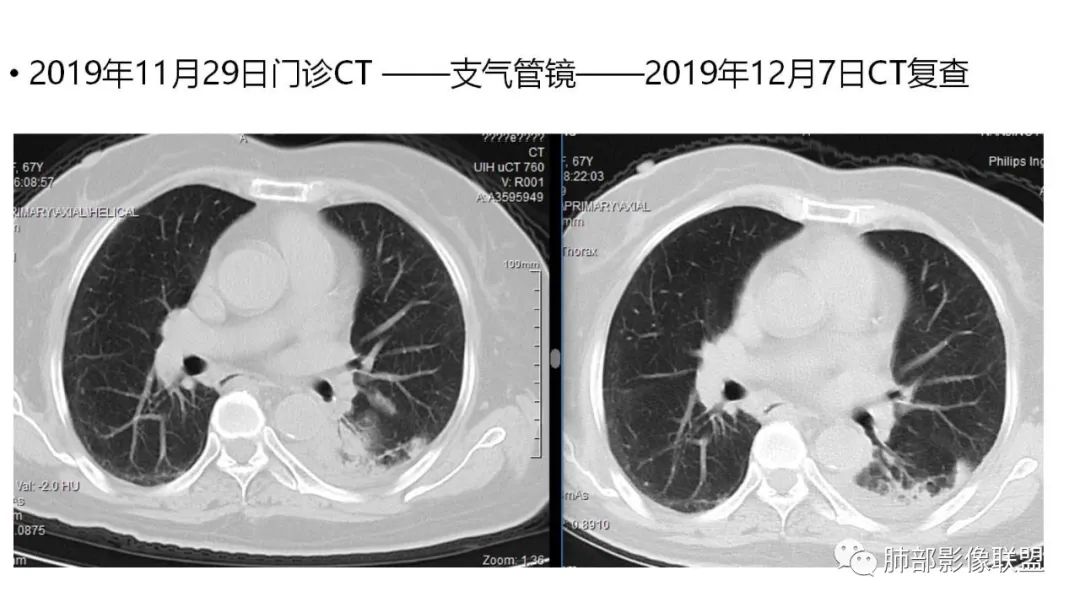

2、病灶常有一个主病灶,常位于下肺。后沿气道播散为多发病灶。

9.粘液腺癌的变化规律:结节缓慢发展而来,向周围播散形成斑片后可快速进展,有时支气管镜后或粘液排出后局部可形成好转的假象。病灶可沿肺泡和支气管播散。

4.回到本例,左下肺病变两次好转,均未经过肿瘤治疗,第一次是支气管镜后,第二次是当其他病变都在进展的情况下,左下肺病变范围反而缩小趋于浅淡。